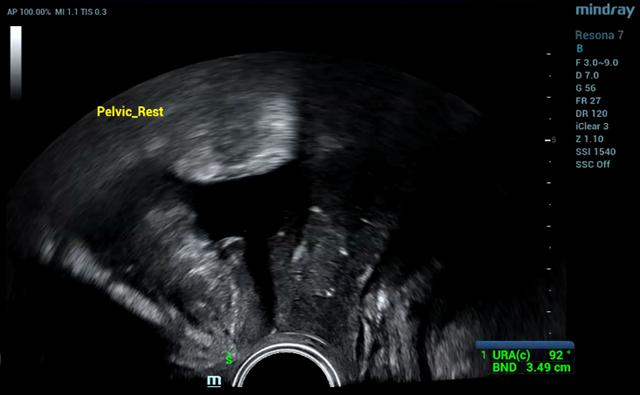

智能临床应用-智能盆底测量

智能超声时代已经到来,智能化超声系统提供标准化的诊断切面、精准化的诊断数据、最大化提升医生诊断效率,成为超声医生忠实的诊疗伙伴,成为医生的左膀右臂,作为超声科室的临床医生,期待人工智能助力SUI早期筛查,期待智能超声造福人类,与医生齐心协力守护人类健康,让超声医生更有价值、更受尊敬。